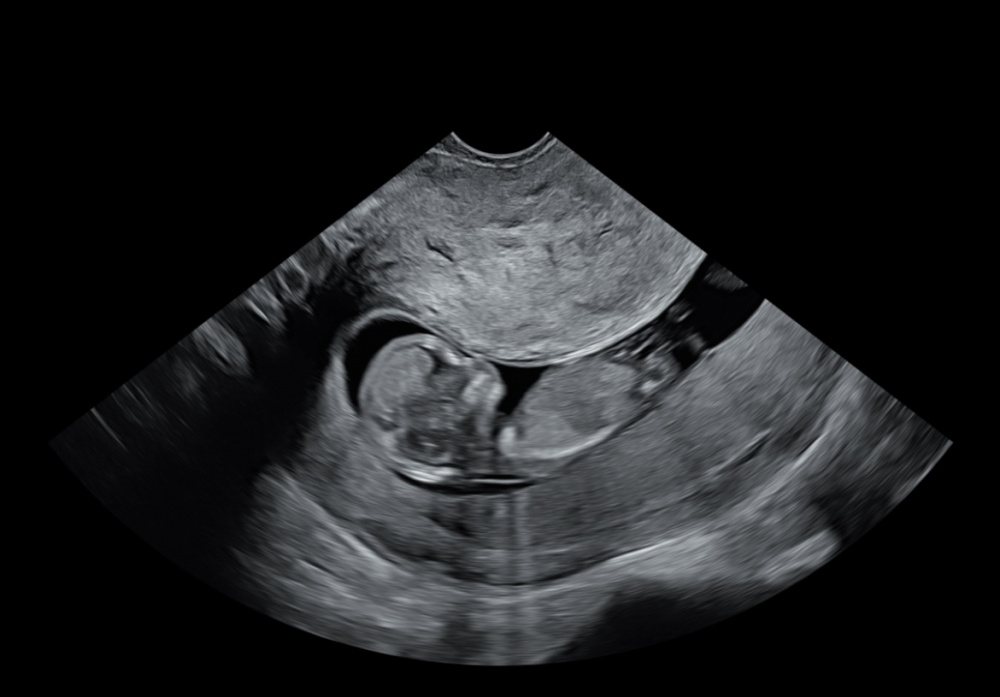

vllt habt ihr ja eine Vermutung nach was für einem Geschlecht die Ultraschallbilder aussehen. 🙂

Das erste Bild ist von 11+2 und das zweite Bild von12+3

Kann man da überhaupt etwas erkennen?